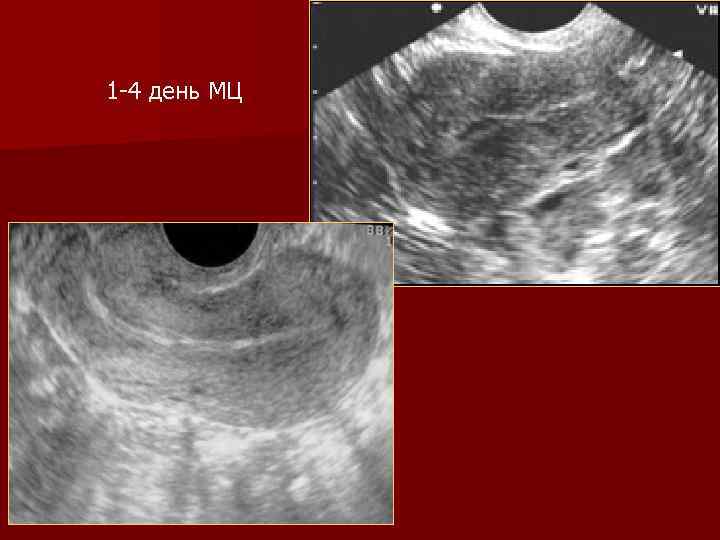

1 -4 день МЦ

Морфологические изменения Эндометрия n I фаза: - десквамации и регенерации (1 -3 -4 дни) - пролиферации (4 -14 дни) n II фаза: секреции (15 -28 дни)

Первая фаза менструального цикла Влияние эстрогенов n М-эхо представлено тремя гиперэхогенными линиями n Эндометрий гипоэхогенный n Увеличение толщины М-эхо n